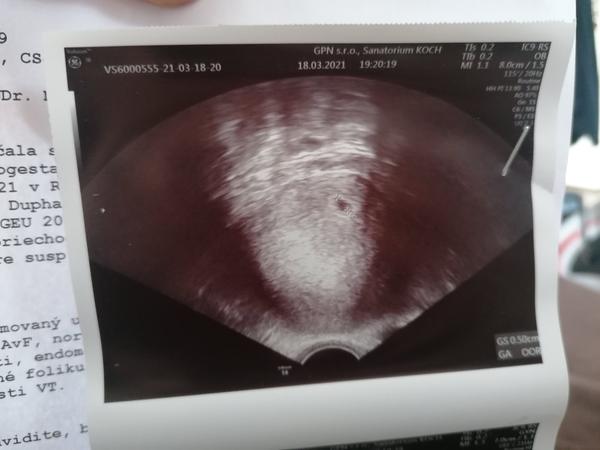

Ahojte baby nám sa zatiaľ to tak vyzerá prvé iui podarilo, mam prve sono za sebou. Ale mam obavy, Totiž začala som slabo spinit tak na ružovo, utekala som na pohotovosť na súkromnú kliniku. Lekár tam nič nevidel že len slabú linke ružové čosi. Ze krvácanie prvom trimestri je taka záhada ale vraj problém nevidí bola som tam vo štvrtok večer. Na Sone len gestacny vak ale to som bola 4tt+6, zobrali hcg a v piatok ráno mi volali ze je 2077, 6dni dozadu bolo 51. Bojím sa ale stále toho špinenie a prázdneho vaku totiž 2017 som mala mmt a bojím sa opakovania co si myslite je to ôk? Pripadne aký ste mali vy v tom čase obrázok? Ďakujem krásne za odpovede